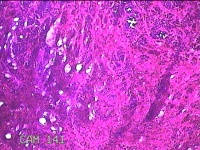

右侧头皮结节

性别

男

年龄

28岁

临床诊断

皮肤良性肿瘤

一般病史

发现右侧头皮结节3个月余,无明显疼痛及不适。

标本名称

大体所见

灰白暗红色组织1.5x1.2x0.8cm一块,表面带梭形皮肤1.5x1cm,皮下见结节1.5x1x0.3cm一个,结节表面有少许毛发,切开结节呈实性,切面灰白粉红色,质软。